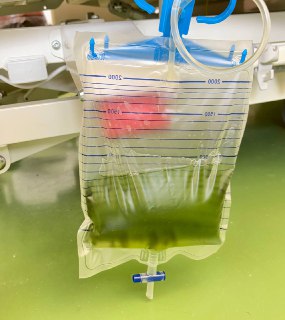

Декомпесанція СН з гідротораксом вправо. Думали пунктувати, але спочатку вирішили титрувати діуретики і терапію СН і вий...

Жінка 69 років Скарги: задишка, набряки При огляді: набряки до стегон, анасарка, ортопное, сатурація 90% + Додаю екг...

Сьогодні пощастило зафіксувати рідкісний побічний ефект пропофолу 🫣 зелений колір сечі